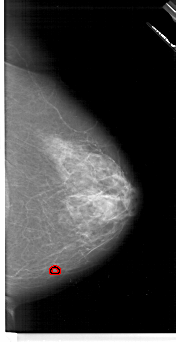

A_1622_1.LEFT_MLO

LEFT_MLO LINES 6301 PIXELS_PER_LINE 3646 BITS_PER_PIXEL 12 RESOLUTION 43.5 OVERLAY

FILE: A_1622_1.LEFT_MLO.OVERLAY

TOTAL_ABNORMALITIES 1

ABNORMALITY 1

LESION_TYPE MASS SHAPE IRREGULAR MARGINS SPICULATED

ASSESSMENT 5

SUBTLETY 5

PATHOLOGY MALIGNANT

TOTAL_OUTLINES 2

BOUNDARY

CORE